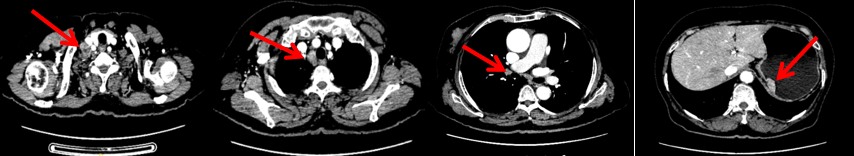

颈胸腹盆腔CT

右乳外上象限占位,考虑乳腺癌;右侧锁骨上、上纵隔及右肺门多发淋巴结转移(较大者24*15mm)。胃贲门处小弯侧胃壁明显增厚(26*12mm),考虑胃癌可能,周围脂肪间隙清;颈部未见明确异常。头颅MR未见脑转移。

2023.6.26复查PET-CT

1.右乳外上象限乳腺癌病灶(22*16mm),对比2023-04-14 CT(26*24mm)较前缩小,FDG代谢活跃。右侧腋窝小淋巴结(5mm),较前稍缩小,代谢不活跃。右侧锁骨上区、上纵隔淋巴结转移瘤(24*18mm),现大小同前相仿,代谢活跃(SUV:6.7)。

2.现胃贲门部术后改变,术区未见明显异常活性灶。

3.左乳、左侧胶窝术后改变,未见明显异常活性灶。双肺小结节。考虑炎性结节可能,建议复查;双肺门及纵隔另反应性淋巴结。